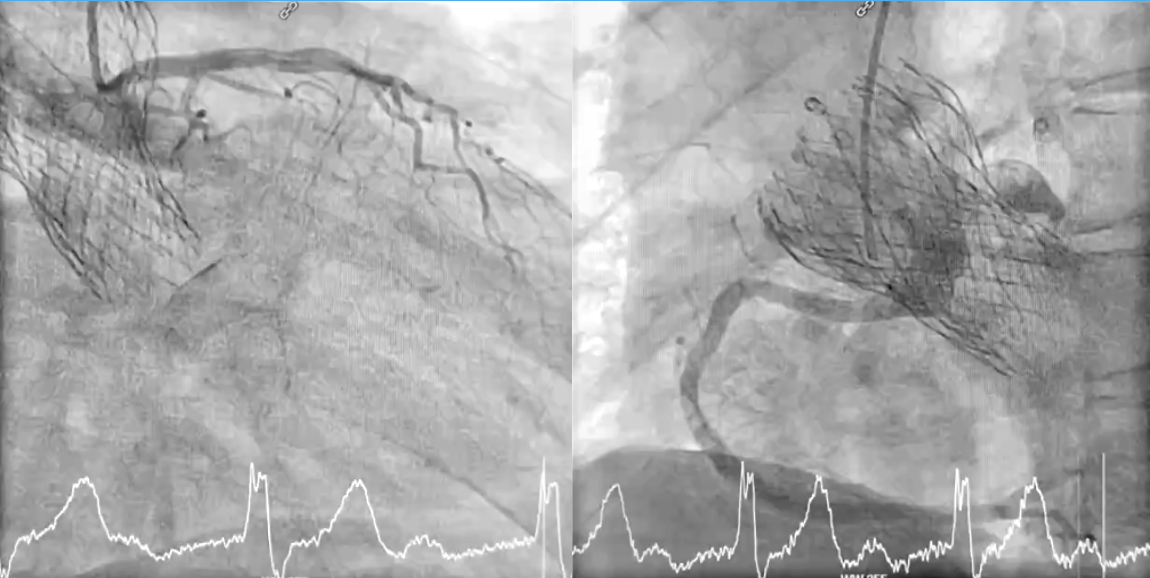

CT confirmed absence of commissural misalignment of failed CoreValve, and commissural alignment of the Evolut PRO was achieved by orienting the delivery system with the flush port at 3 o¡¯clock. The inflow portion of the the Evolut PRO was implanted at the same level as the failed CoreValve. Aortography post-implantation confirmed no RCA obstruction.

To mitigate the risk of coronary obstruction, the RCA was protected using a coronary guidewire and balloon. CT confirmed absence of commissural misalignment of failed CoreValve, and commissural alignment of the Evolut PRO was achieved by orienting the delivery system with the flush port at 3 o¡¯clock. The inflow portion of the the Evolut PRO was implanted at the same level as the failed CoreValve. Aortography post-implantation confirmed no RCA obstruction, allowing safe removal of the guidewire and balloon. The procedure was uneventful, with no conduction disturbances or paravalvular leak. The functional mitral regurgitation resolved immediately after the procedure.

Case Summary